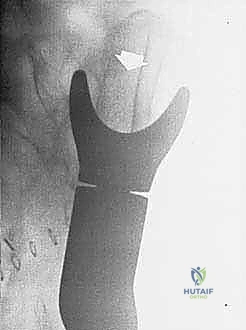

- Plain Radiography (FIG 2): While of limited value for early lesions, it provides an initial overview. As you can see in Figure 2A, we have a large lytic lesion of the right periacetabular region. Figure 2C shows a cartilage-forming lesion in the left ilium. However, plain films often underestimate the true extent of these tumors.

* CT with Intravenous Contrast and 3D Reconstruction (FIG 3): This is our workhorse for assessing bone involvement, destruction, and the critical relationship between the tumor and major pelvic blood vessels. It reveals any distortion of the pelvic anatomy and guides resectability. Figure 3A clearly shows extensive bone destruction and tumor extension into the pelvis and gluteal region. Figure 3C highlights an extensive tumor on the medial aspect of the ilium with destruction of the inner table.